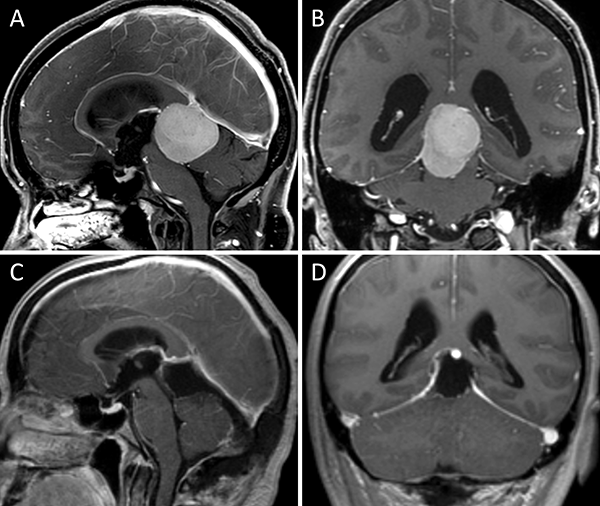

Figura 1. Meningioma tentorial medial. A-B: RM preoperatoria; C-D: RM postoperatoria.